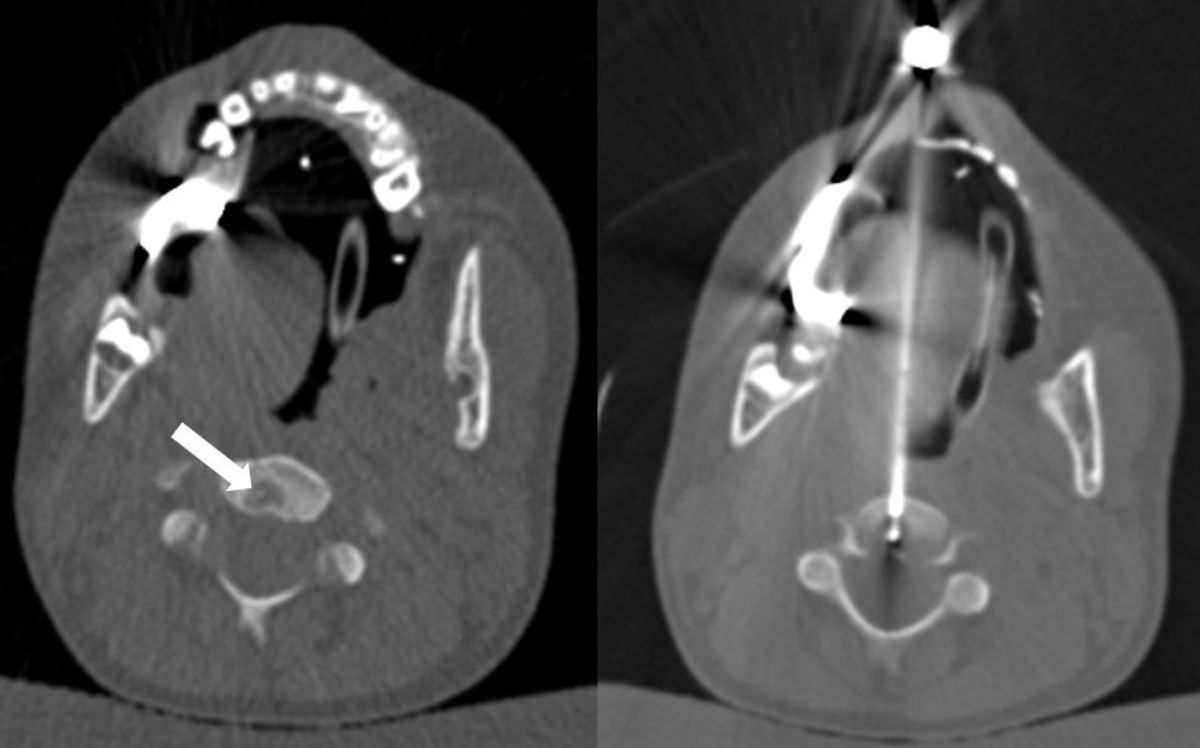

Auch die Radiofrequenzablation wird vorgestellt. Dank dem modernen Verfahren konnte kürzlich ein äusserst schmerzhafter Knochentumor im 2. Halswirbel eines 6-Jährigen zielsicher und schonend mit Radiowellen (hochfrequente elektrische Energie bzw. Strom) behandelt werden. Noch vor einigen Jahren wäre eine Operation mit grossen Risiken verbunden gewesen. Dank der Möglichkeiten der modernen Bildgebung war der kleine Patient bereits am Folgetag des minimalinvasiven Eingriffs schmerzfrei.

Computertomografie der erfolgreichen Radiofrequenzablation des Osteoidosteoms des jungen Patienten.